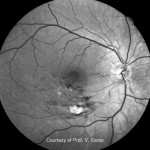

Image Galleryサンプル画像ギャラリー

画像ギャラリー

Courtesy of Prof.G.Staurenghi, Prof.S.Sadda, Prof.V.Sarao